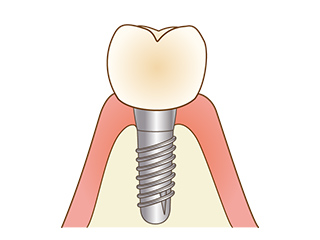

インプラントは、人工の歯根を埋め込み、人工の歯を装着することで失ってしまった歯を取り戻す治療方法です。

見た目の改善だけではなく、ご自身の歯と同じようにしっかりと噛むことができるため、機能面の回復も期待できます。

できあがった被せ物を土台に装着して治療は完了です。